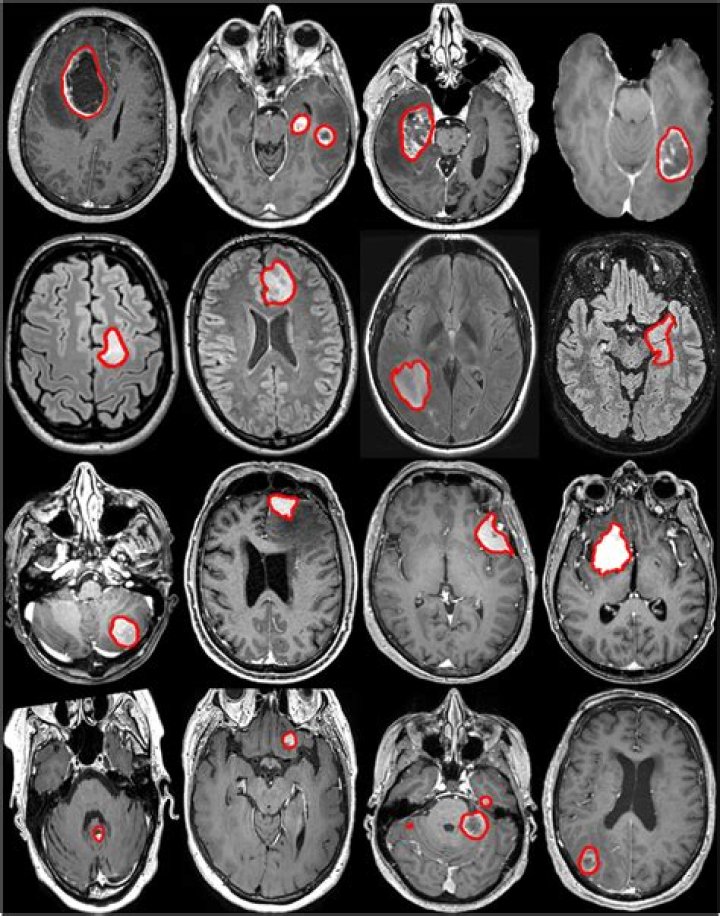

• Brain tumors.

MRI can be used to detect brain tumors, traumatic brain injury, developmental anomalies, multiple sclerosis, stroke, dementia, infection, and the causes of headache.